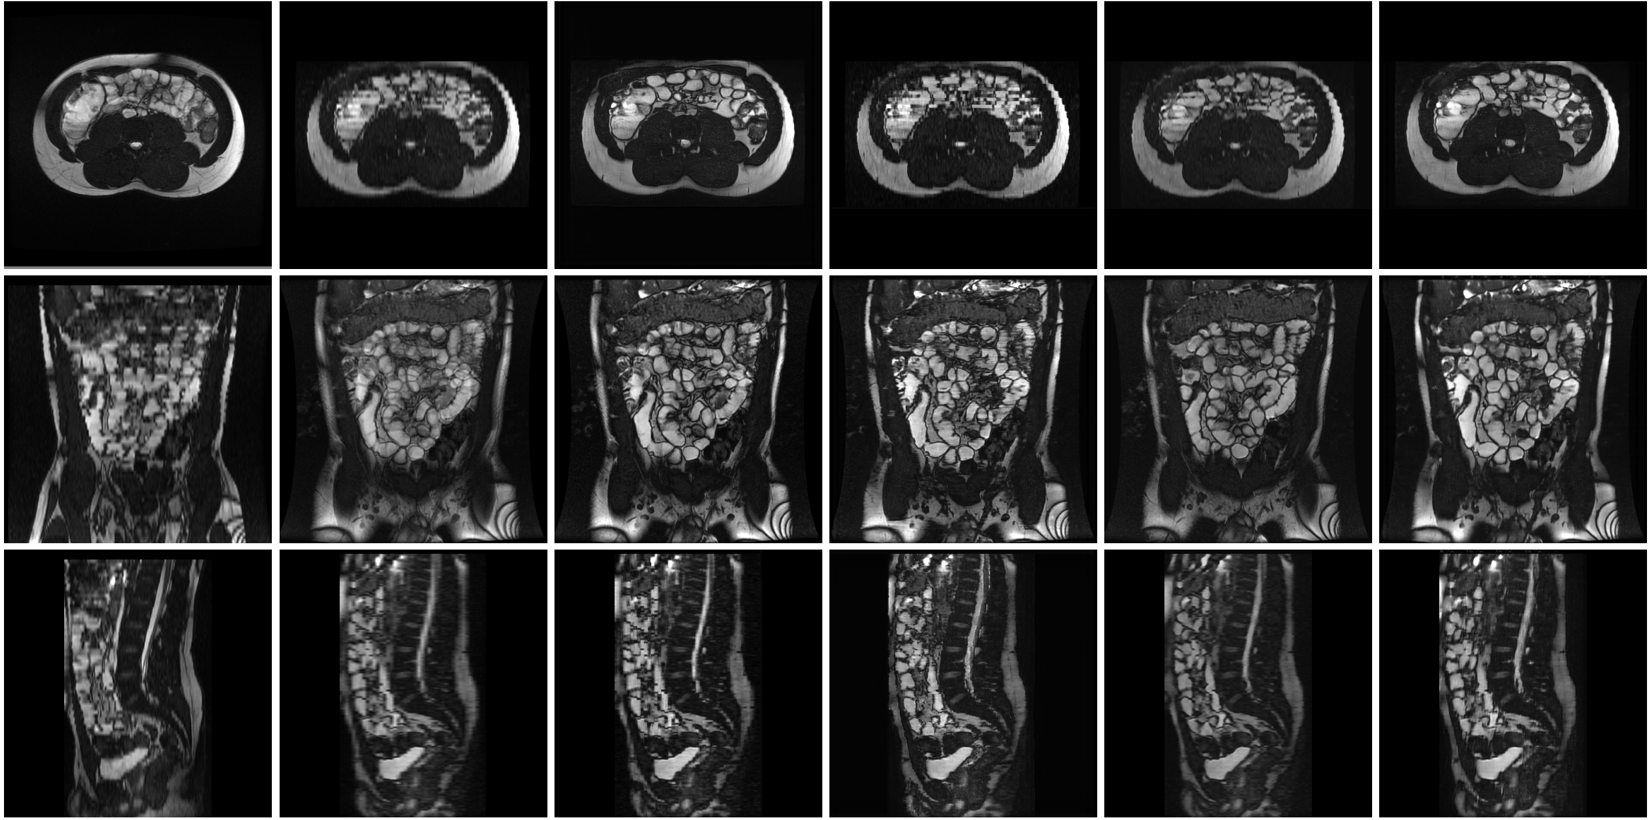

Refer to captionAxial VolumeCoronal VolumeAxial ATMECoronal ATMESMORE4SIMPLE Axial View Coronal View Sagittal View

Figure 3: Multi-plane view of slices sampled from the isotropic MRI volume generated by SIMPLE in comparison to five competitive methods (from left to right): linear interpolation on anisotropic axial volume, linear interpolation on anisotropic coronal volume, ATME on anisotropic axial volume, ATME on anisotropic coronal volume, SMORE4 on anisotropic coronal volume, and SIMPLE on anisotropic coronal volume. Our approach, SIMPLE, produced higher-quality slices simultaneously on all planes compared to the other methods, which produced high-quality slices along the super-resolution plane but resulted in artifacts in the other planes.

Multi View Slices:

Figure 3 presents views of the three primary planes of isotropic MRI volumes generated by SIMPLE and five other methods. SIMPLE effectively enhances quality and resolution in both axial and coronal planes, unlike methods that favor a specific plane. Interpolation and ATME improve the plane quality corresponding to their original anisotropic acquisition. Both SIMPLE and SMORE4 improve resolution and quality across all planes but SIMPLE excels in the axial plane by better detecting and sharpening edges and improving contrast. In the coronal plane, the differences between SIMPLE and SMORE4 are subtle, with some organ locations differing. Additionally, SMORE4 is sensitive to organ shadows and emphasizes noise. Although SIMPLE has no constraints on the sagittal plane, it improves resolution similarly to SMORE4, which does have such constraints.